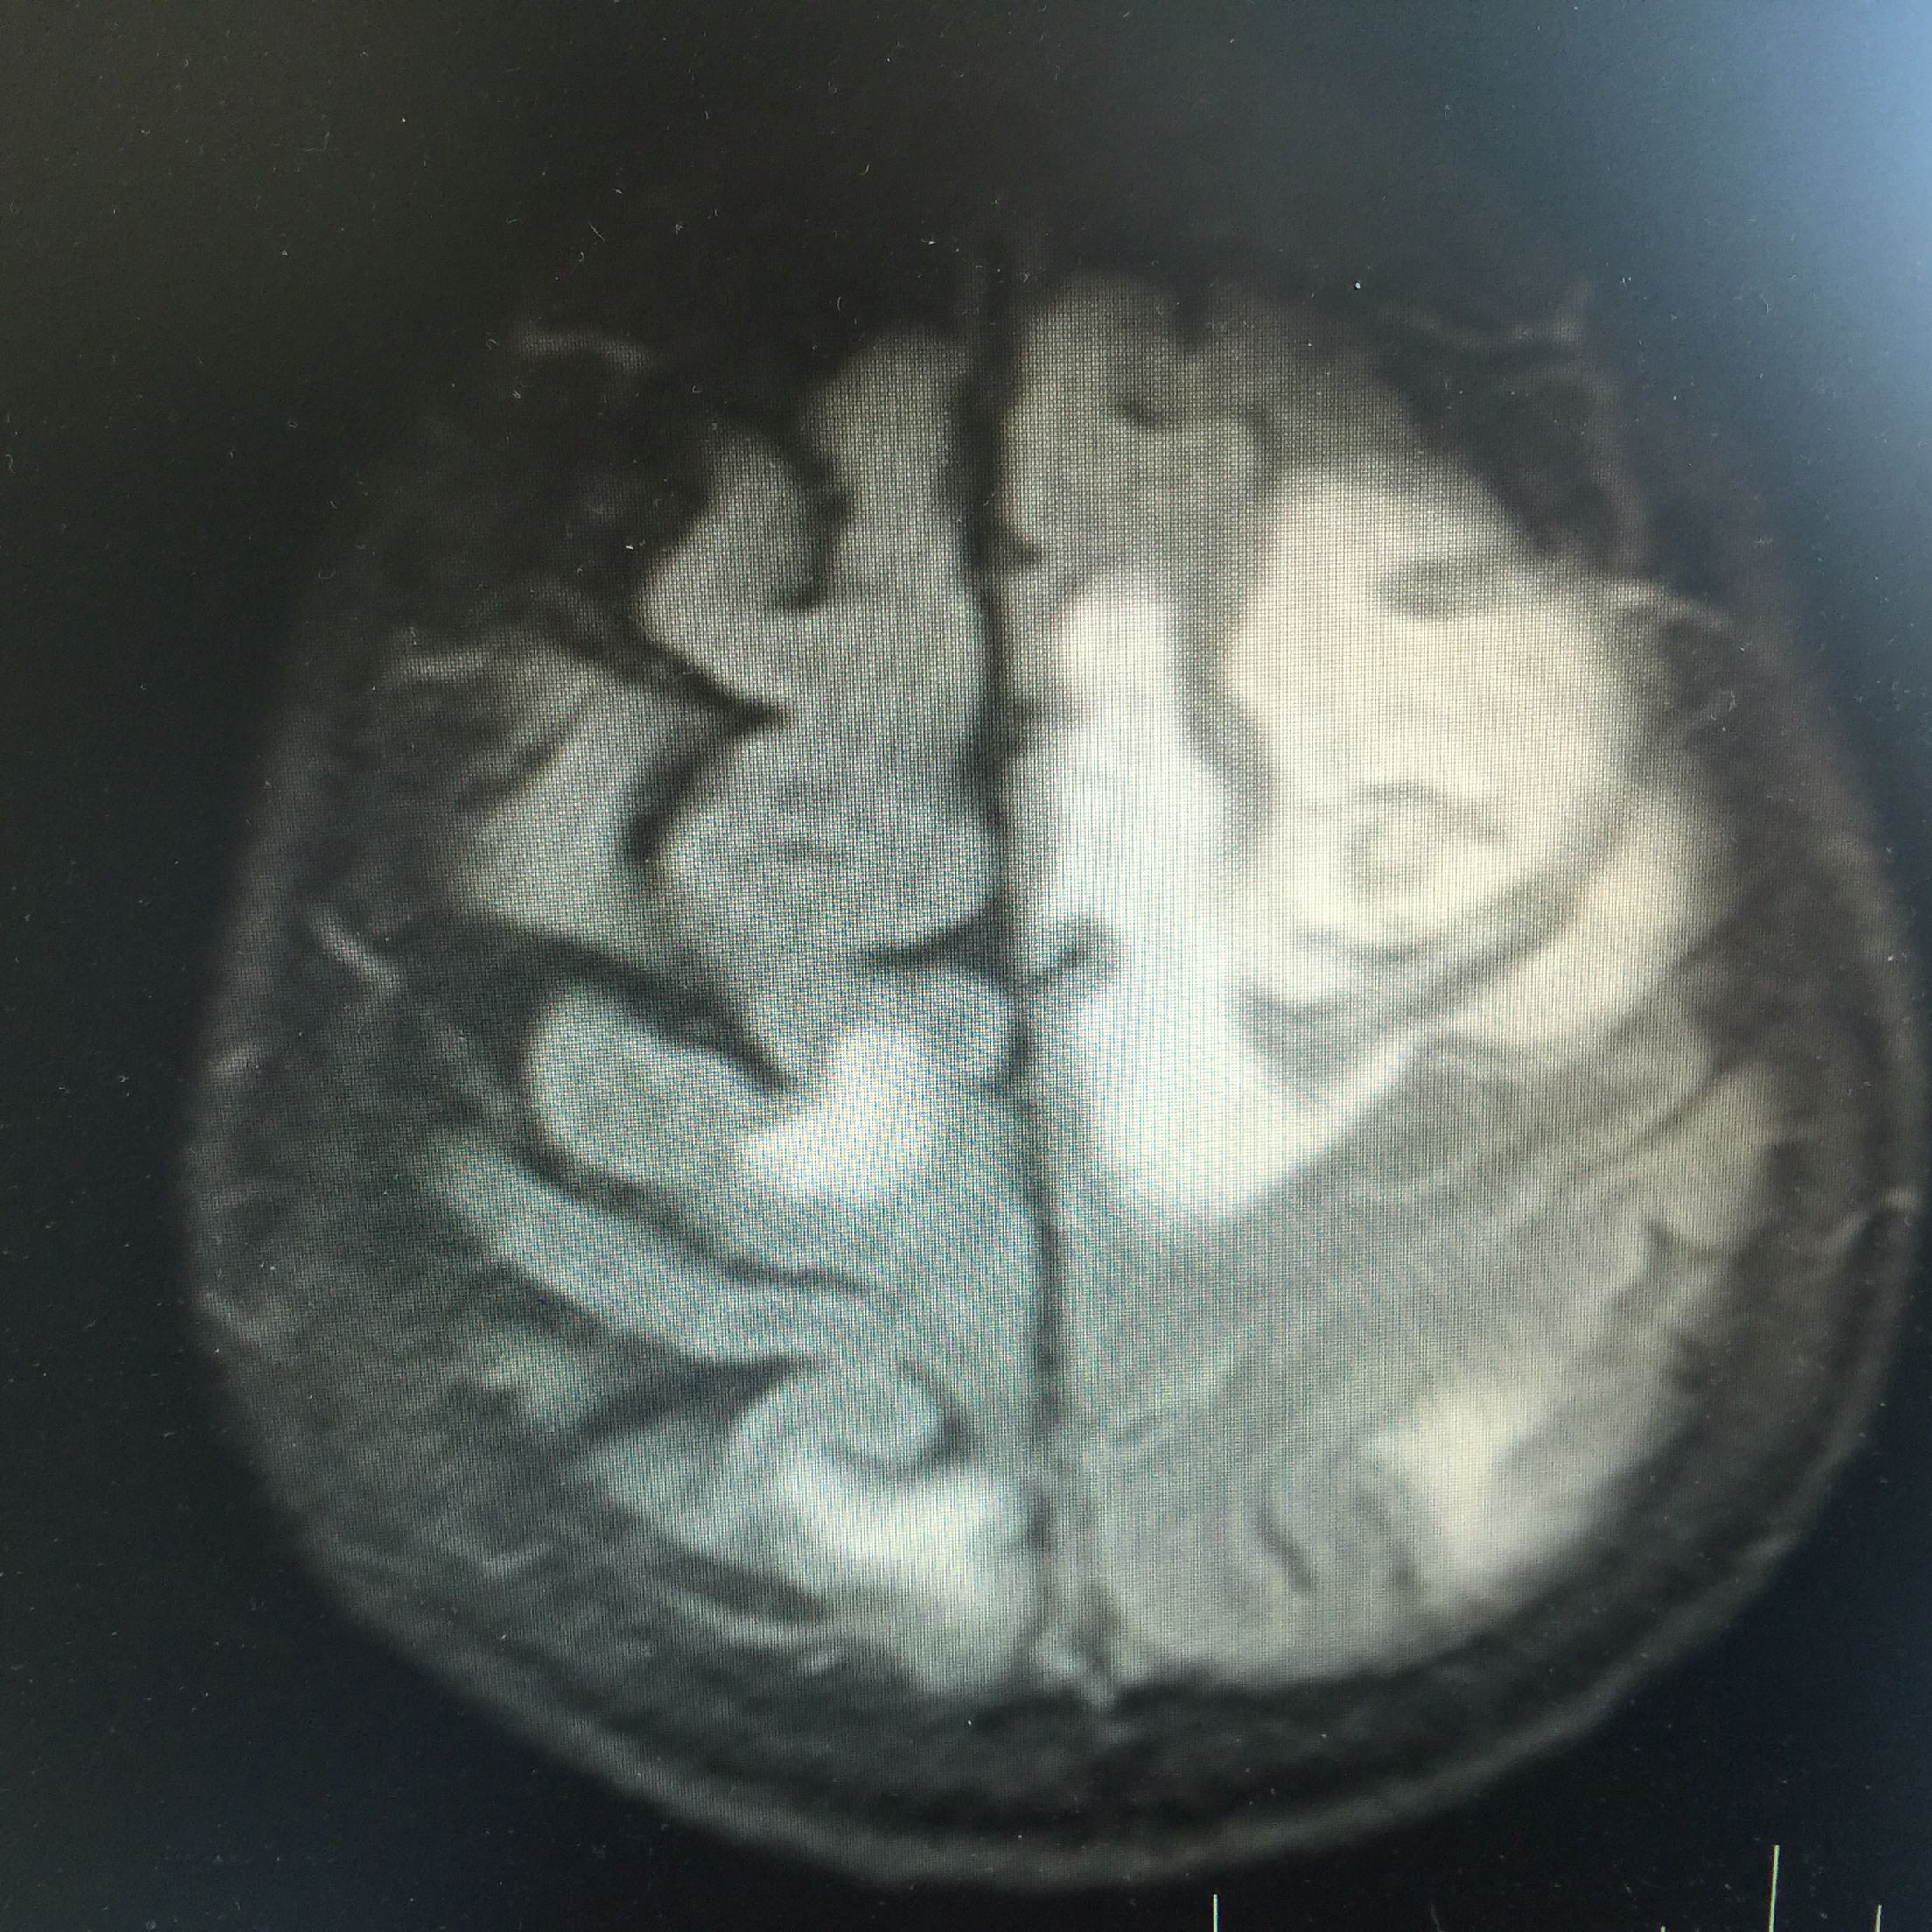

1.女,81岁,以“右侧肢体无力3天”入院。 2.现病史:3天前无诱因出现右侧肢体无力,右上肢抬举费力,右下肢步行拖拉,无抽搐,无意识障碍! 3.既往史:2016年肺穿刺活检,免疫组化为腺癌!已合并第五、六椎体转移、左肾上腺转移,行灌注介入治疗。

查体:血压:130/80mmHg,两肺呼吸音清,未闻及啰音,心率98次/分,律齐,未及杂音,双下肢无水肿。神经系统查体:意识清,双侧瞳孔等大正圆,直径约3.0mm,对光反射灵敏,无面舌瘫,右侧肢体肌力4级,腱反射减弱,Babinski征R+L-。

左肺腺癌 骨转移、双肺门及纵膈淋巴结转移、左肾上腺转移、脑转移! 治疗:对称、支持治疗!